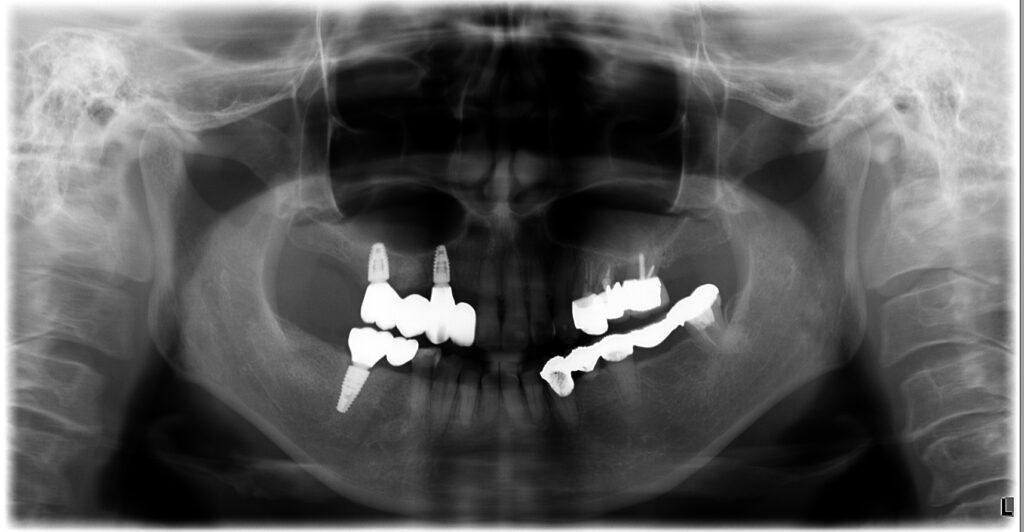

当院では、インプラント本数を絞って上下ともにブリッジ設計とし、さらに部分矯正で前歯の噛み合わせを作り直すことで、少ない本数でも成立するように調整。

結果として、抜歯即時で“オペ1回”で完結させた症例です。

- 上下ともにインプラントブリッジで噛める機能を回復

- 患者様の希望に合わせ、外科は抜歯即時で1回にまとめた

治療の工夫④:抜歯即時で“オペ1回”にまとめる

患者様の「手術が怖い」「回数を減らしたい」という希望に対して、

条件が許す範囲で抜歯と同日にインプラント埋入(抜歯即時)を行い、外科介入を1回にまとめました。